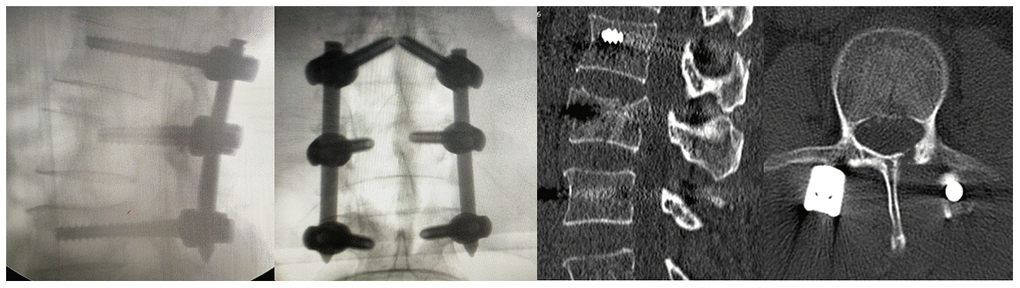

Lumbar posterior decompression and fixation was performed in a laminar flow, negative pressure operating room. All procedures were performed while strictly adhering to biosafety level 3 standards. In addition to routine personal protection, goggles were worn and postoperative disinfection was performed. The surgery took around 1 hour and 30 minutes, and there were 200 ml of blood loss without blood transfusion. After the surgery, the patient was transferred to the intensive care unit for medical observation and treatment. On the second postoperative day, the patient was safely returned back to the ward with a lumbar brace. Postoperative radiography and CT revealed that the internal repair was well positioned (Figure 3).

Figure 3. Postoperative X-rays and CT examination of the patient.